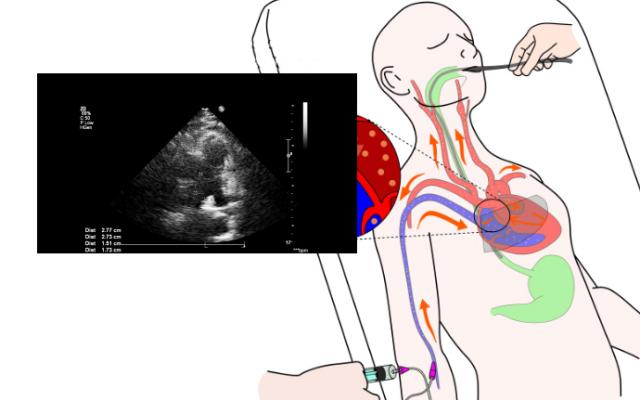

Un ecocardiograma transesofágico (ETE) es un procedimiento que utiliza el ultrasonido para producir imágenes en movimiento en tiempo real del interior del corazón. En un ETE, la sonda de ultrasonido se coloca en su esófago (el tubo que va desde la boca al estómago), para tomar las imágenes de su corazón. Puede ayudar a diagnosticar problemas cardíacos.

Un ecocardiograma transesofágico se utiliza para revisar la estructura de su corazón y para ver cómo está funcionando. El procedimiento usa una sonda de ultrasonido para obtener una imagen en movimiento de su corazón. Transesofágico significa que se toman imágenes desde el interior del esófago, el tubo que une la boca al estómago.

Es posible que deba permanecer en el hospital algunas horas para un ETE. El procedimiento de un ecocardiograma transesofágico se lleva a cabo en una habitación privada y se le puede pedir que se coloque una bata de hospital. Se le rociará una anestesia local en la parte trasera de la garganta para entumecerla y ayudarle a tragar la sonda de ultrasonido.

También le podrán administrar un sedante inyectable que lo ayudará a relajarse y aliviar la ansiedad. Se le dará un protector bucal de plástico para resguardar sus dientes. Se le pedirá que se acueste de lado y que trague una pequeña sonda, la cual se encuentra en el extremo de un tubo flexible. Podrá respirar normalmente.

La sonda emite ondas de ultrasonido, las cuales rebotan en las estructuras de su corazón y son recogidas por la máquina de ecocardiograma. Las imágenes de su corazón se mostrarán en una pantalla. Cuando haya terminado la prueba, su médico sacará suavemente el tubo.